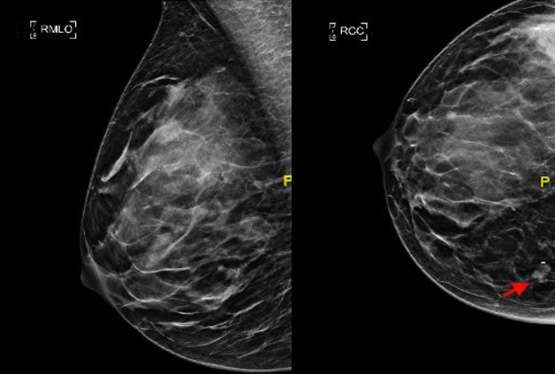

In the ideal craniocaudal view, the nipple should be positioned midline and the length of the PNL should be within 1 cm from that of the MLO view (Figure 1). The image receptor is positioned beneath the breast and compression is applied superiorly. When positioned correctly, the craniocaudal view has the advantage of showing the deep medial breast tissue which is often excluded on the mediolateral oblique view. Thus, it is imperative to ensure adequate inclusion of the deep medial breast in the CC view to detect masses that are otherwise excluded in MLO views (Figure 2).

Mass with adjacent microclip is visible in the deep medial breast

Figure 2: The importance of capturing medial breast tissue on the craniocaudal view. A mass with adjacent microclip is visible in the deep medial breast (red arrow) on the craniocaudal view but is not included on the mediolateral oblique view.